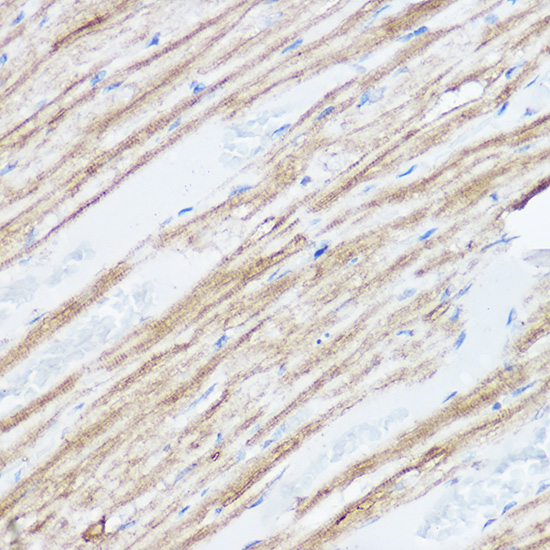

Immunohistochemistry of paraffin-embedded mouse heart using MGLL Rabbit pAb.